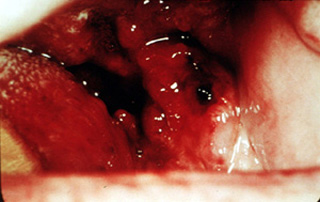

Cáncer grande

El crecimiento continuado de un carcinoma pequeño puede producir una lesión de esta naturaleza que involucra

gran parte del piso de la boca. Es una situación sumamente seria en esta fase, aunque el cáncer no es particularmente grande. Hay

una gran posibilidad de metástasis de los ganglios, que desgraciadamente, es a menudo bilateral cuando los tumores están en

la linea media. La terapia, incluso para este cáncer relativamente pequeño, debe ser

extensa y debilita al paciente.